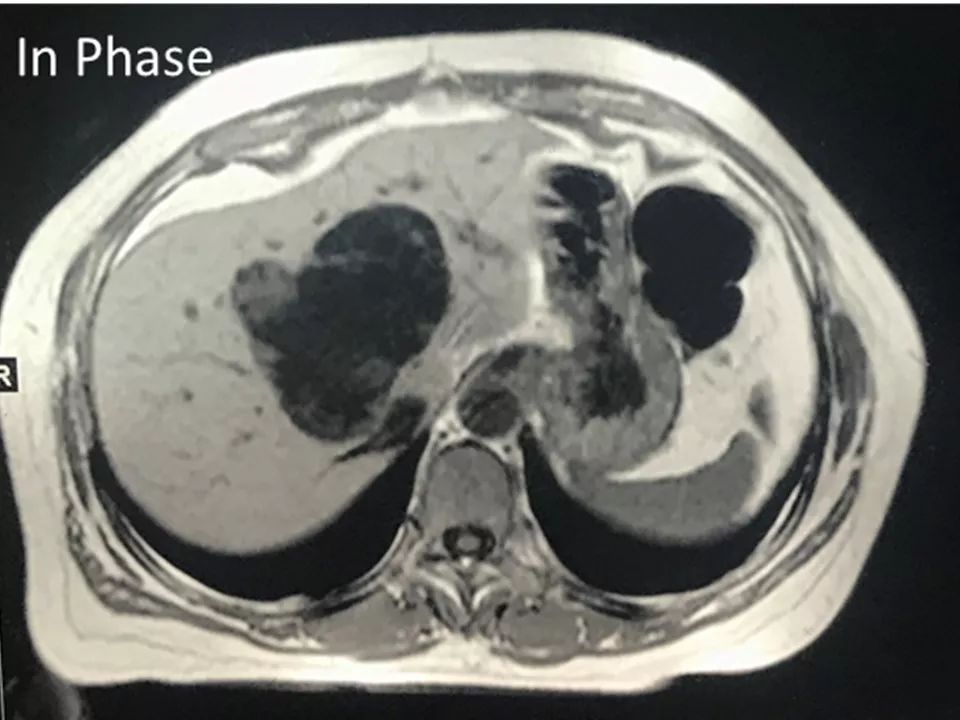

MRI表现:

肝内单发占位灶,累及肝左右叶及尾叶。T1WI示病灶以低信号为主,边缘多枚等信号结节,正反相位未见明显脂肪成份;T2WI示病灶以粘液成份为主呈高信号,边缘多枚稍高信号结节(相对肝实质),DWI呈不均匀等高信号,ADC图以高信号为主。动脉期病灶边缘均匀强化,壁结节显著强化,门脉期边缘仍持续强化,边缘光滑,壁结节呈相对等低信号。MRCP示胆管扩张,病灶与胆管相通。